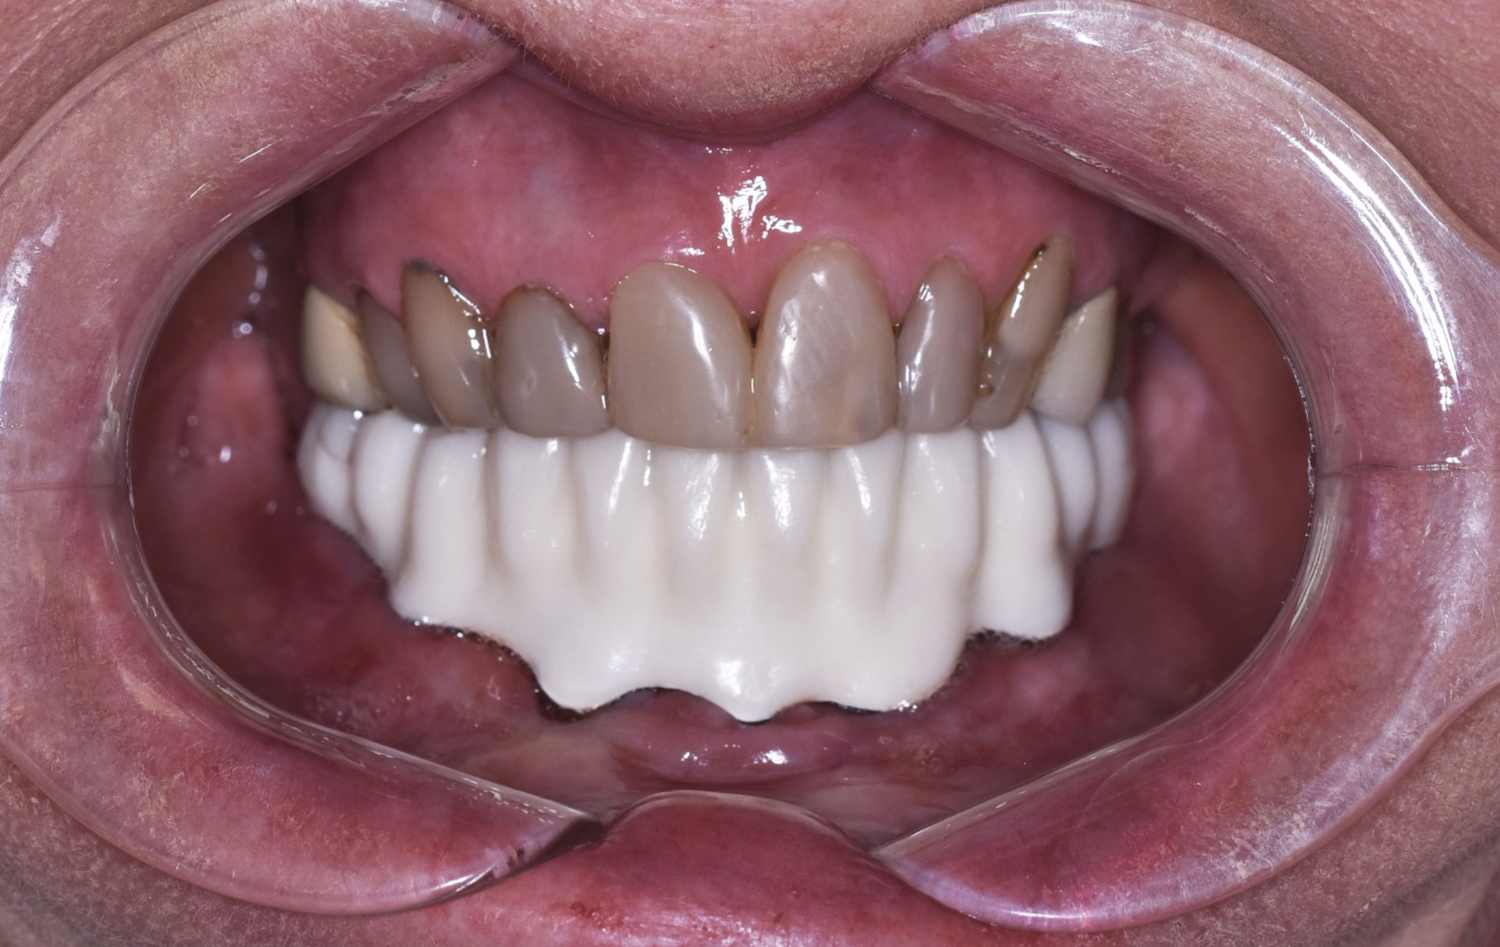

2. Zkouška tvaru a přesnosti v definitivním anatomickém tvaru pomocí bílého resinu nebo frézovaného či tištěného PMMA ✅

Zkouška přesnosti a tvaru pomocí PMMA

Pomocí PMMA je konečný výsledek Branemarku kompletně předem vyzkoušený a odsouhlasený lékařem i pacientem.

Při odevzdávání tedy nehrozí žádné překvapení.